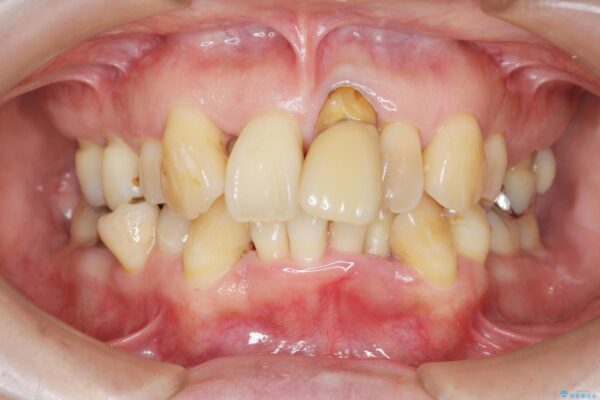

治療中

歯の総合的なマネージメントを行う包括的歯科治療の実践[ 歯周病・矯正・セラミック補綴 ] 治療中画像 歯の総合的なマネージメントを行う包括的歯科治療の実践[ 歯周病・矯正・セラミック補綴 ] 治療中画像 歯の総合的なマネージメントを行う包括的歯科治療の実践[ 歯周病・矯正・セラミック補綴 ] 治療中画像 歯の総合的なマネージメントを行う包括的歯科治療の実践[ 歯周病・矯正・セラミック補綴 ] 治療中画像 歯の総合的なマネージメントを行う包括的歯科治療の実践[ 歯周病・矯正・セラミック補綴 ] 治療中画像 歯の総合的なマネージメントを行う包括的歯科治療の実践[ 歯周病・矯正・セラミック補綴 ] 治療中画像 歯の総合的なマネージメントを行う包括的歯科治療の実践[ 歯周病・矯正・セラミック補綴 ] 治療中画像 歯の総合的なマネージメントを行う包括的歯科治療の実践[ 歯周病・矯正・セラミック補綴 ] 治療中画像 歯の総合的なマネージメントを行う包括的歯科治療の実践[ 歯周病・矯正・セラミック補綴 ] 治療中画像 歯の総合的なマネージメントを行う包括的歯科治療の実践[ 歯周病・矯正・セラミック補綴 ] 治療中画像 歯の総合的なマネージメントを行う包括的歯科治療の実践[ 歯周病・矯正・セラミック補綴 ] 治療中画像

まず、保存の難しい歯を抜去したのち矯正治療を行い歯並びの改善、歯周ポケットを除去したことで安定した歯周環境、咬合関係を作り出すことができました。

矯正治療を事前に行ったことで全ての歯の神経を温存しセラミックブリッジを装着することができました。